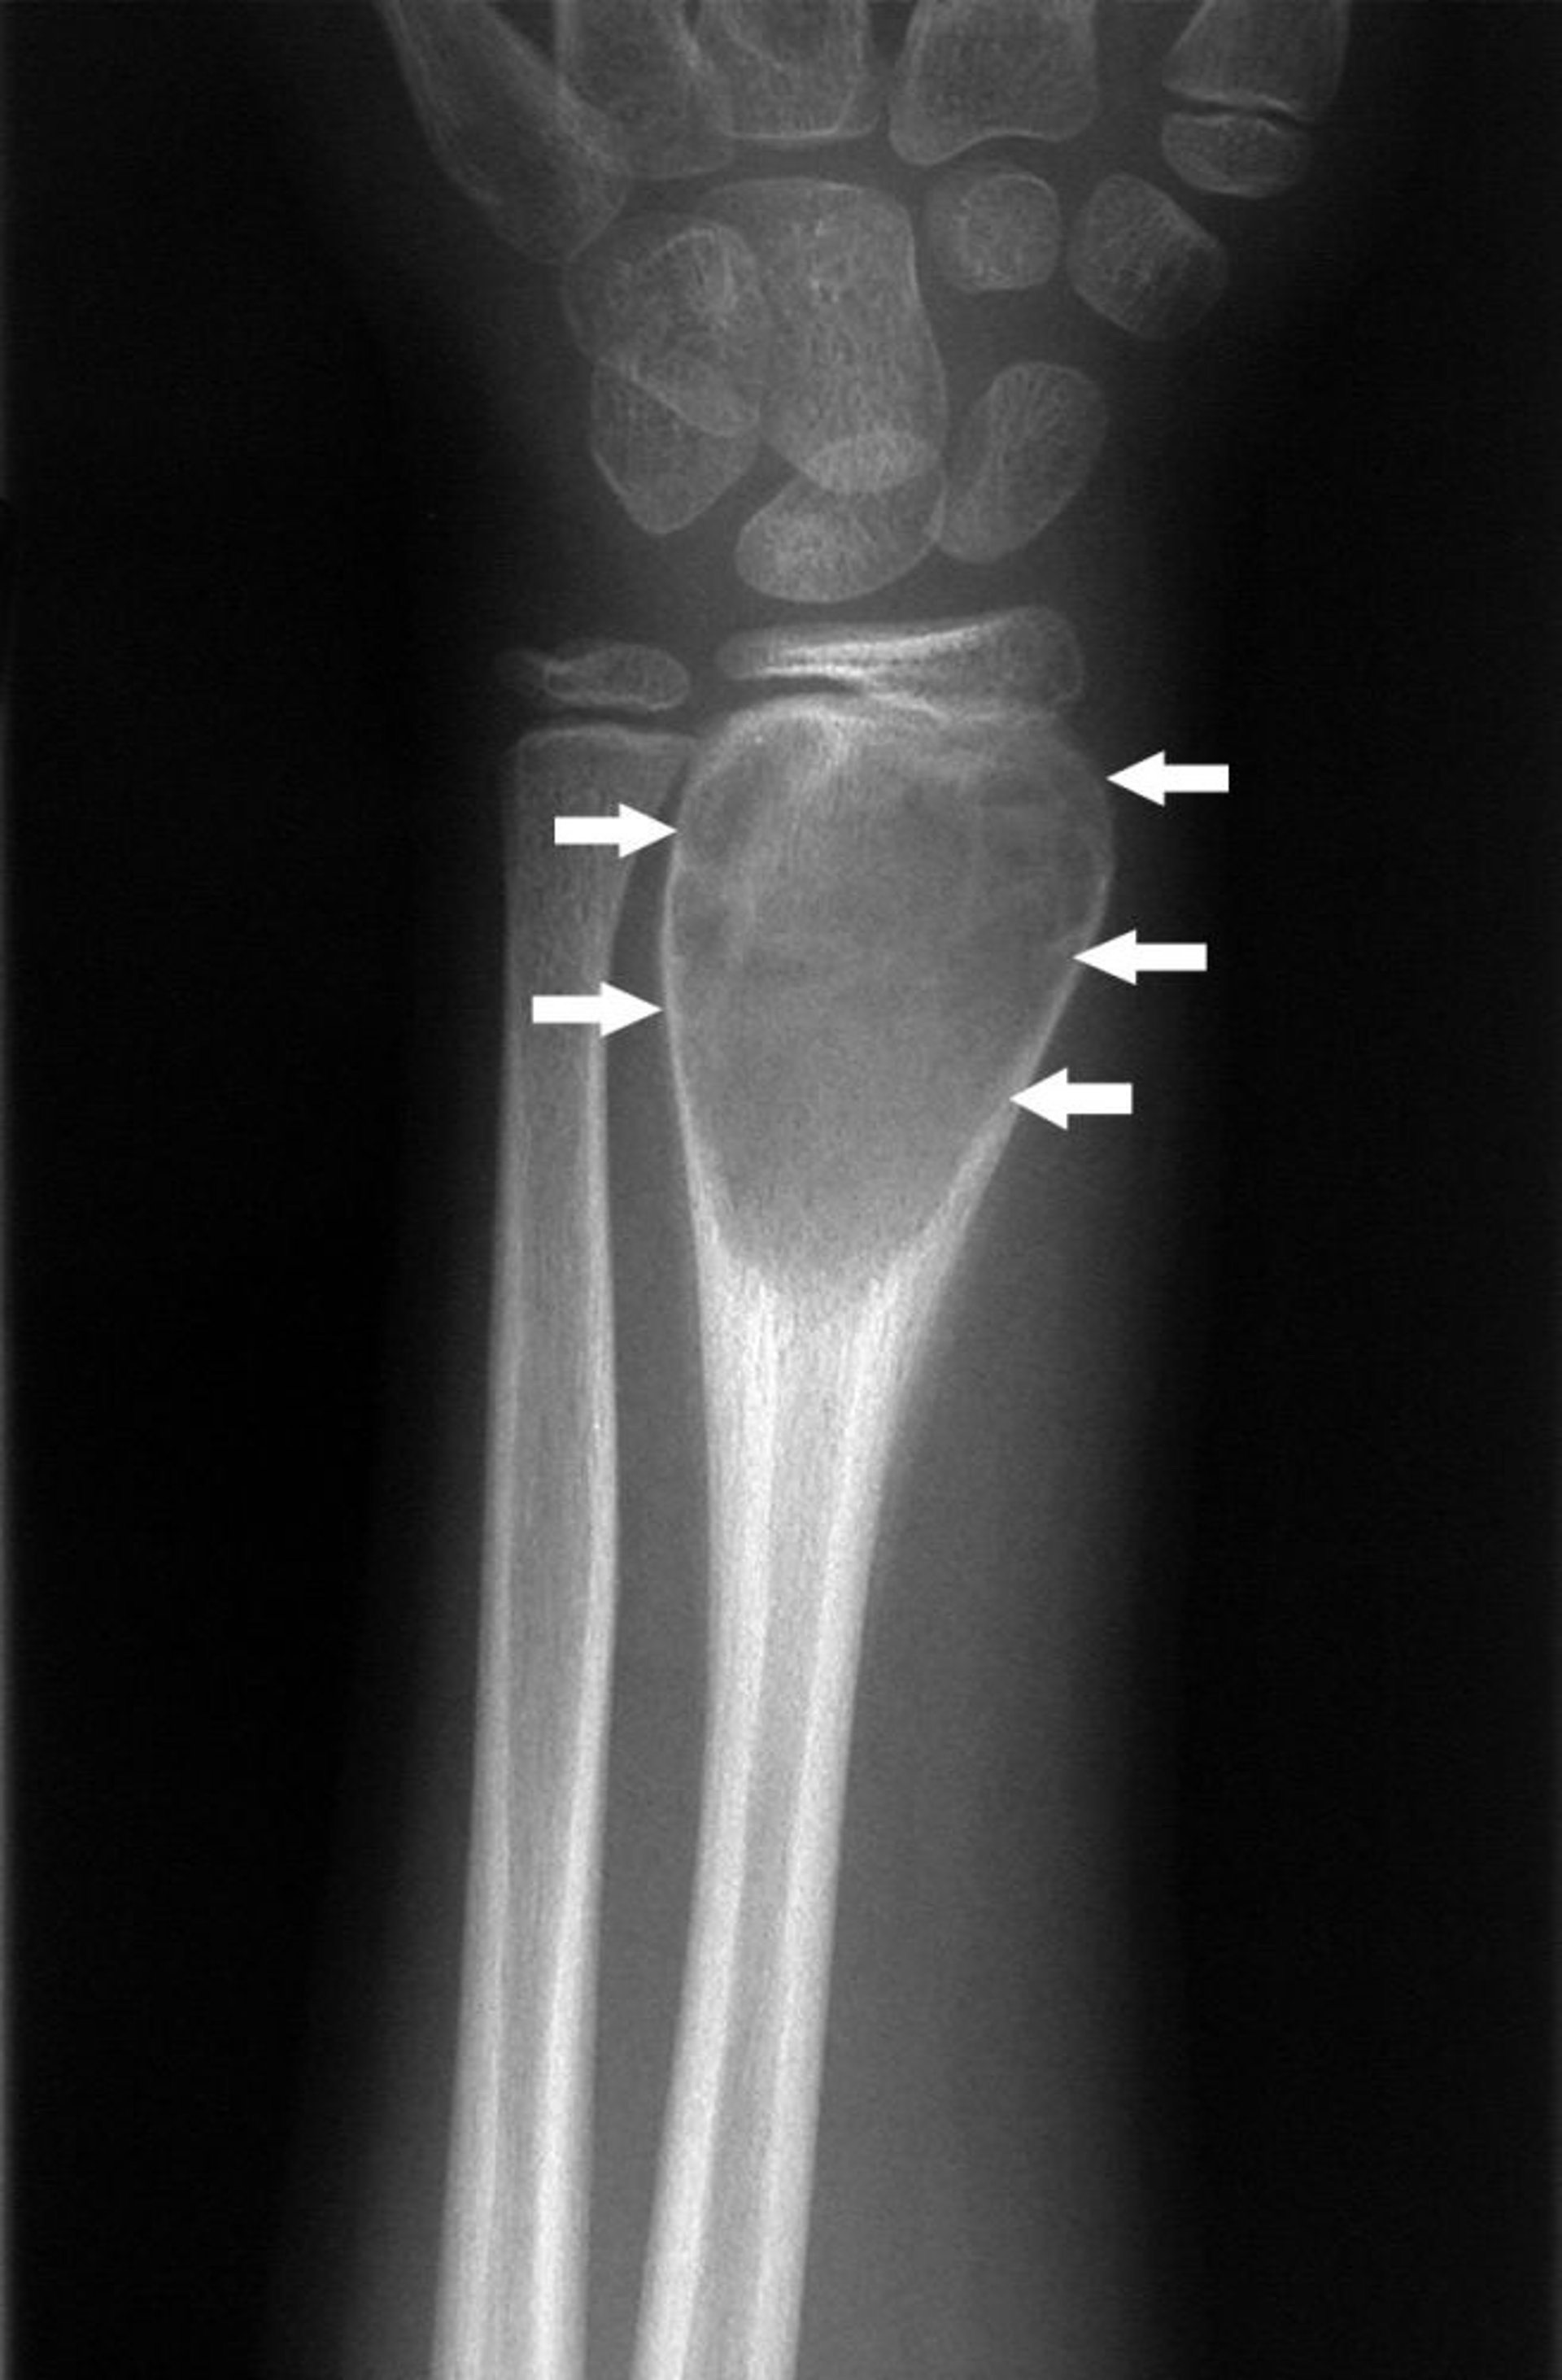

Radiografia del polso che mostra una cisti ossea aneurismatica (frecce).

Per gentile concessione di Michael J. Joyce, MD e Hakan Ilaslan, MD.